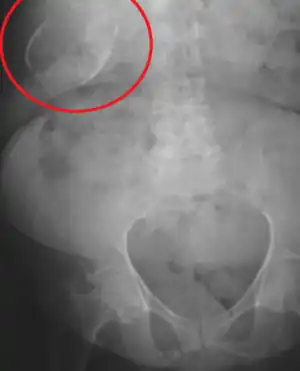

![]() | |

| Porcelain gallbladder on X-ray | |

Porcelain gallbladder is a calcification of the gallbladder believed to be brought on by excessive gallstones, although the exact cause is not clear. As with gallstone disease in general, this condition occurs predominantly in overweight female patients of middle age. It is a morphological variant of chronic cholecystitis. Inflammatory scarring of the wall, combined with dystrophic calcification within the wall transforms the gallbladder into a porcelain-like vessel. Removal of the gallbladder (cholecystectomy) is the recommended treatment.

Abdominal radiography (X-ray), abdominal ultrasound or CT scan.